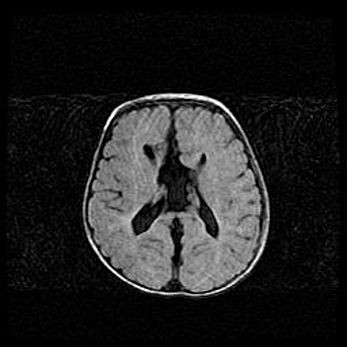

Открытая гидроцефалия.

Возраст: 9 месяцев 12 дней

Вес: 6800 г

Пол: мужской

Окружность головы: 41,5 см

Срок гестации: 28 недель

Гидроцефалия головного мозга у новорожденных имеет характерный признак: опережающий рост окружности головы приводит к визуально хорошо определяемой гидроцефальной форме сильно увеличенного в объёме черепа. Детские неврологи определяют следующие симптомы гидроцефалии у грудничков: выбухающий напряжённый родничок, частое запрокидывание головы, смещение глазных яблок к низу.